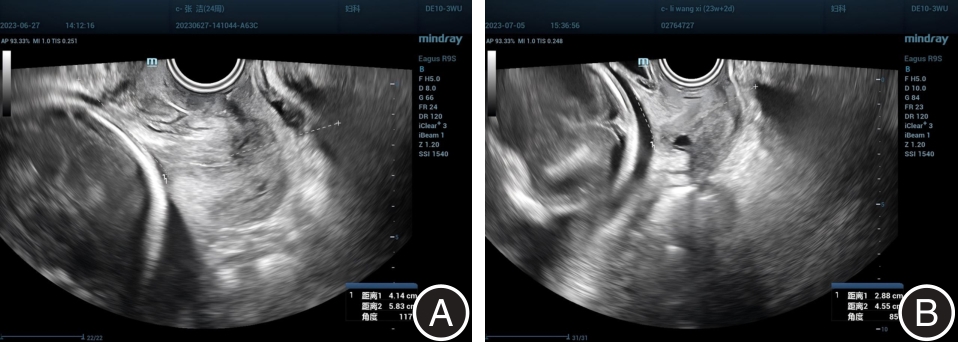

Minsui CAI,Qi CUI,Sujun DING,Xuejun. NI. Application value study of cervical shear wave elasticity imaging combined with cervical length and anterior cervical angle in assessing cervical function and predicting spontaneous preterm birth[J]. The Journal of Practical Medicine, 2025, 41(6): 896-903.